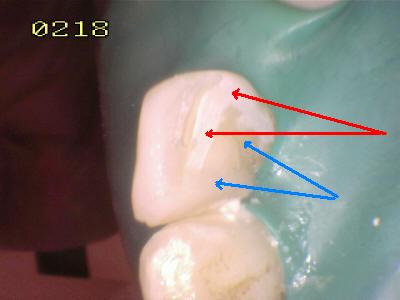

Procedimiento

de cementado, se debe tener cuidado de eliminar los excesos de

cemento (flechas blancas) antes de su endurecimiento; dado que el espesor de

cemento puede ser importante por la desadaptación por caries.